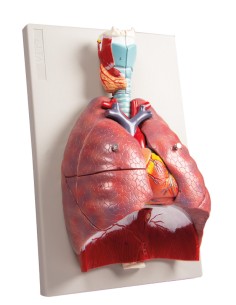

Du crâne en 22 parties à verrouillage magnétique aux modèles de colonne vertébrale, des modèles d'articulation aux modèles de cœur, chaque pièce de notre collection est conçue pour une immersion totale dans l'étude de l'anatomie humaine. Nos modèles, réalisés à partir de scans d'os réels, garantissent une expérience tactile authentique et une fidélité de poids presque identique aux originaux.

Indispensables aux étudiants comme aux professionnels, nos modèles anatomiques sont des outils pédagogiques qui permettent d'observer les structures anatomiques avec précision, en évitant les dissections ou les études invasives. Ils sont également utiles pour expliquer les pathologies aux patients, ce qui rend la communication plus efficace et permet de gagner un temps précieux.